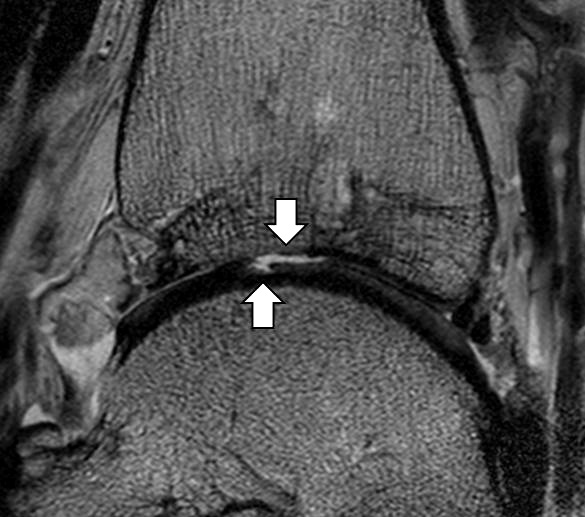

b. T2 fs axial. Infraktion des hinteren Volkmann‘schen Dreiecks (schmale, weiße Pfeile). Hier inserierende, intakte, hintere Syndesmose (breite, weiße Pfeile).

Abbildung 18b

Das Ligamentum tibiofibulare posterius (hintere Syndesmose) verläuft flacher und geht nach kranial in das Ligamentum tibiofibulare interosseus und nach kaudal in das Ligamentum intermalleolare posterius über. Letzteres bildet ein artikuläres Labrum zwischen Trochlea und Talus 9.

Da also die hintere Syndesmose an der posterioren Tibia inseriert, entspricht eine Fraktur oder Infraktion des hinteren Volkmann`schen Dreiecks funktionell einem knöchernen Ausriss des Ligamentum tibiofibulare posterius (Abb. 18 a und b). Aufgrund der Koinzidenz von Syndesmosenläsionen mit Innenbandverletzungen ist bei der Beurteilung gesondert auf solche zu achten.